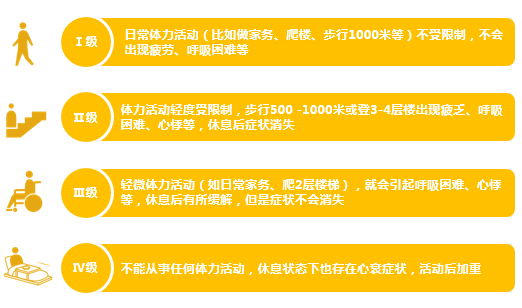

♥NYHA分级(纽约心功能分级):用来评价心功能受损的程度。按照诱发心衰的活动程度把心功能的受损状况分为四个等级,I级最轻,IV级最严重。NYHA分级帮助心衰患者和医生简易地了解心功能受损和病情严重程度,可以帮助选择合适的检查、治疗方案。